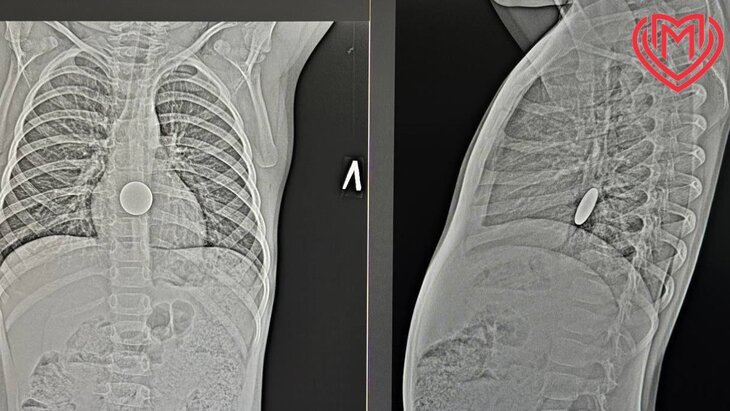

Фото: департамент здравоохранения Москвы

Специалисты городской клинической больницы имени Кончаловского оказали помощь ребенку, проглотившему монету. Об этом сообщили в пресс-службе департамента здравоохранения Москвы.

В результате проведенного обследования врачи обнаружили, что инородный предмет не попал в дыхательные пути четырехлетнего мальчика, а застрял в его пищеводе. После точного определения расположения объекта хирурги успешно вытащили монету за несколько минут.